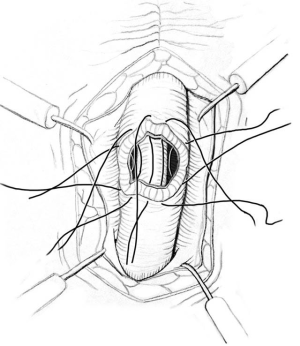

ISU is performed at the time of AUS device explantation. Figure 1 shows an endoscopic view of the eroded AUS cuff. After the cuff is removed, Foley catheter is inserted to facilitate reconstruction, and when necessary, urethroscopy with wire placement ensures accurate placement of a 14-French Council tip catheter (Figure 2). ISU is accomplished by reapproximating the urethral defect with full-thickness, interrupted 2-0 absorbable monofilament suture over the catheter (Figures 3 and 4). This abbreviated approach is performed without further mobilization of inflamed tissues within the already hostile operative field. The urethral Foley catheter is left in place for three weeks with voiding cystourethrogram (VCUG) imaging done at the time of removal.

We thank Elsevier for the permission of reprinting Figure 3.